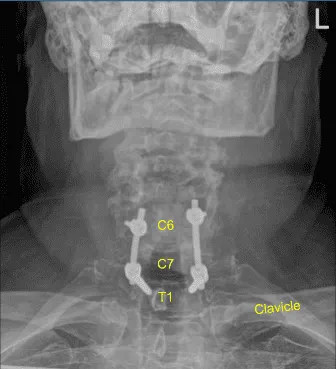

Image-guided stereotactic frame with neuronavigation techniques were used to place the instrumentation. We placed bilateral T1 pedicle screws and decorticated with electric high-speed drill cannulating with the navigated pedicle finder, palpating for breaches, measuring the depths, under tapping by 11 mm and placing 30 mm x 5.0 mm titanium pedicle screws bilaterally without difficulty.

Next, we placed bilateral lateral mass screws at C6. Inspecting the deformity of the spine, a decision was made not to place the C5 lateral mass screws because of kyphotic deformity and difficulty with rod placement.

So, we next decorticated the joints at C6-C7 and C7-T1 and bilateral T1 transverse processes with electric high-speed drill for the arthrodesis. The autograft resected was morselized. Precut-precontoured titanium rods were placed across the tulips from C6 to T1 and secured with locking caps and then final tightened with a torque and anti-torque device.

Morselized autograft and demineralized bone matrix allograft was packed in lateral gutters from C6 to T1 bilaterally. The wound was irrigated copiously until clear. Hemostasis was confirmed.